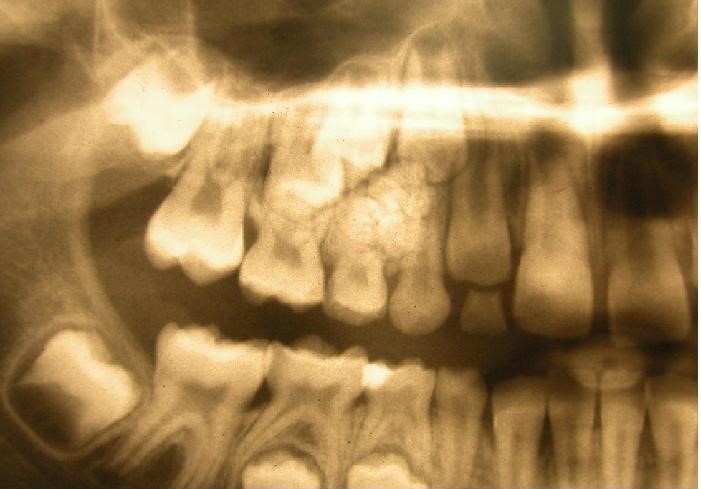

Poniższy obraz rtg przedstawia: